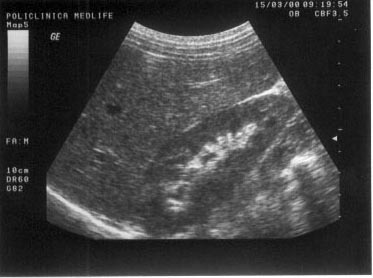

Figura

13. Ovarul st`ng este ]nlocuit de o formaiune complex[, transsonic[ =i

solid[. Partea solid[ ]n proporie de 40%, cu ecostructura hiperecogen[

este dispus[ sub forma de prelungiri papilifere cu contur neregulat =i

prezint[ ]n interior c`teva mici zone transsonice (posibil arii de

necroz[). Aspectul sugereaz[ chistadenocarcinom ovarian.